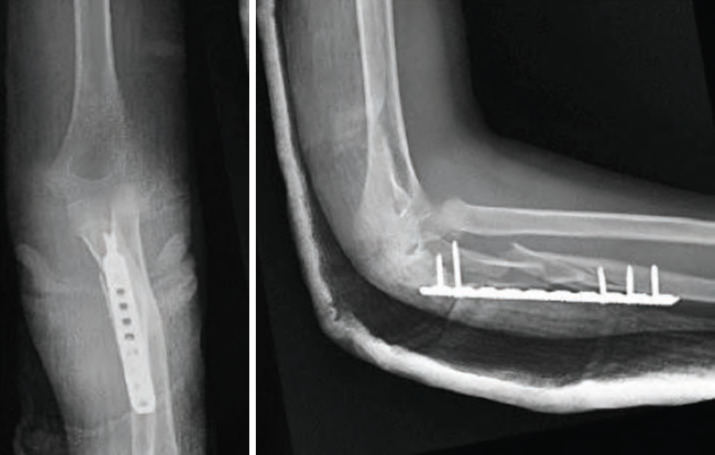

In this case report, we present a 13-years-old patient who sustained a Monteggia equivalent fracture along with an ipsilateral distal radius fracture following a fall on the elbow. Comminuted ulnar fracture was treated with open reduction and internal fixation with a bridging plate. After restoring the ulnar length, the radial neck fracture was successfully reduced. The distal radius fracture was managed conservatively. Our literature review shows that, the patient is one of the comparatively older patients treated with open reduction and internal fixation in this area and that a successful outcome was achieved with early mobilisation. This case underscores the need for further studies to determine the optimal treatment strategy in such cases.